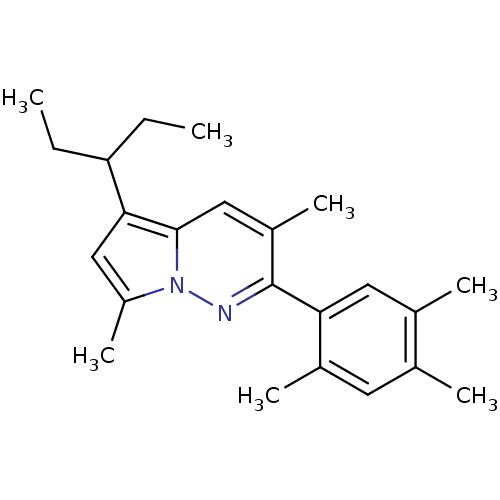

TargetCorticotropin-releasing factor receptor 1(Homo sapiens (Human))

Dupont Pharmaceuticals

Curated by ChEMBL

Dupont Pharmaceuticals

Curated by ChEMBL

Affinity DataEC50: 0.700nMAssay Description:Antagonist activity at human CRF1 receptor expressed in CHO-K1 cells assessed as CRF-stimulated cAMP accumulation by enzyme immunoassayMore data for this Ligand-Target Pair

Affinity DataEC50: 0.700nMAssay Description:Antagonist activity at CRF-R1 in mouse AtT-20 cells assessed as inhibition of human CRF induced cAMP accumulation after 30 mins by radioimmunoassayMore data for this Ligand-Target Pair

Affinity DataEC50: 0.800nMAssay Description:Antagonist activity at CRF-R1 in mouse AtT-20 cells assessed as inhibition of human CRF induced cAMP accumulation after 30 mins by radioimmunoassayMore data for this Ligand-Target Pair